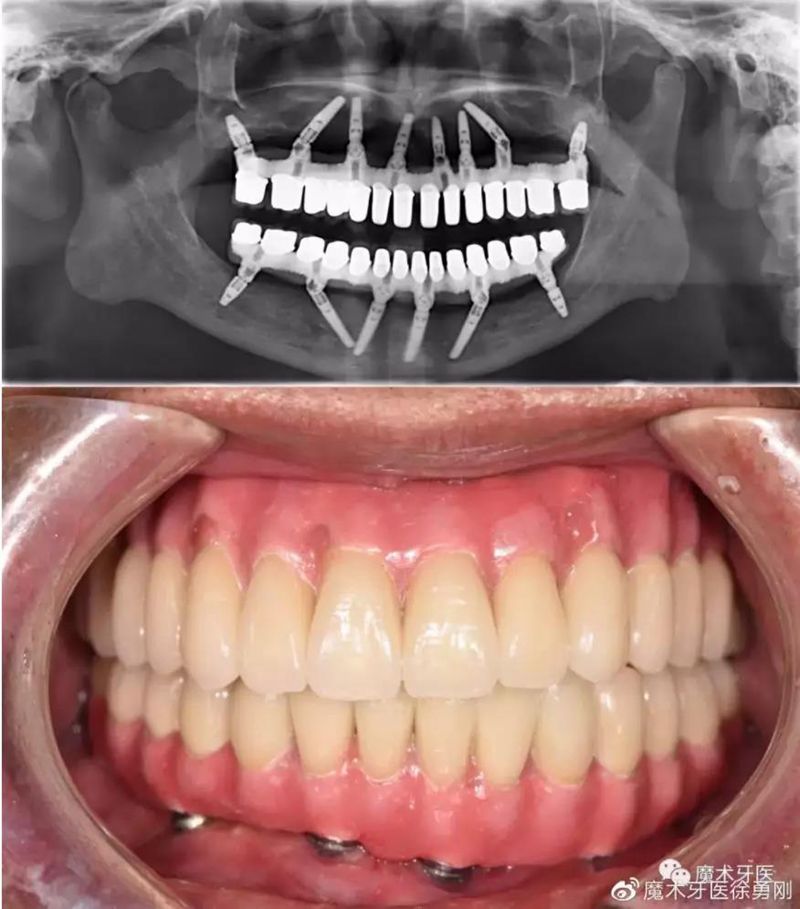

上图是一个30多岁的小伙子牙周炎的最终归宿——全口牙松动,拔除。在口腔大夫那里,这些病例已经司空见惯了,一句话形容:看起来,他们一颗牙也不缺,其实,已经一颗牙也不在了!

牙周炎患者的就诊率低,因素绝不是单一的,有一种观念非常普遍——等牙全部掉光了再镶一口假牙。殊不知,全口活动义齿,功能比天然牙相差一大截,咀嚼效力并不高,使用也不方便,当然,全口种植义齿也是一种选择(如图),可以较好地恢复咀嚼功能,然而,并不是每个无牙患者,都拥有“口腔里开一辆奔驰”的财力。